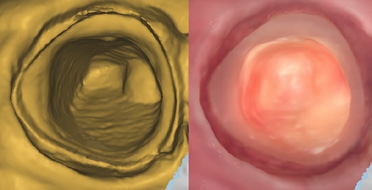

Die Implantatprothetik ist einer der Bereiche, in dem die digitale Abformung eine große Erleichterung für den Zahnarzt darstellt. Die Übertragung der Implantatsituation im Mund war bisher für Patienten und Arzt mit konventionellen Methoden unkomfortabel und schwierig. Durch lange Übertragungspfosten war gerade im Molarenbereich das Entfernen der Abformung häufig schwierig. Zudem war die gleichzeitige Abformung von Implantaten und Zähnen durch Materialverziehungen oft nicht in allen Bereichen präzise, sodass Wiederholungen der Abformung nötig wurden. Diese Problematiken liegen bei der digitalen Abformung nicht vor. Je nach System wird zunächst der Restkiefer inklusive der offenen Implantatschraube gescannt, um das Emergenzprofil darzustellen. Die Übermittlung des Emergenzprofils ist eine Information, die zuvor dem Labor nicht zur Verfügung stand und funktionell wie ästhetisch hochwertigere Ergebnisse ermöglicht. Anschließend wird ein zu Implantatsystem und Implantatgröße passender Scanpfosten eingeschraubt, um die Implantatposition zu übertragen. Dieser wird ebenfalls gescannt. Die Software des Scanners rechnet diesen automatisch in den ersten Scan ein. Nach Abformung des Gegenkiefers und der digitalen Bissnahme ist der Vorgang der Abformung beendet und die Daten können ins Labor versandt werden. Sollten weitere präparierte Zähne in dieser Abformung enthalten sein, können diese natürlich einzeln präzise abgeformt und sofort im Monitor überprüft werden. Auf weitere gnathologische Vermessungen gehen wir hier nicht ein, diese sind aber natürlich analog wie digital möglich.